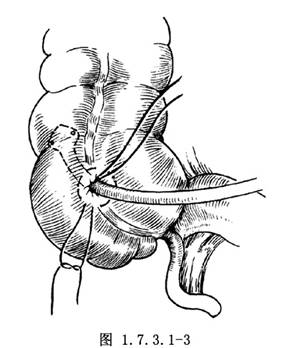

3.取出吸引管,插入一蕈状导管,结扎第1荷包缝线,剪去线尾(图1.7.3.1-3)。